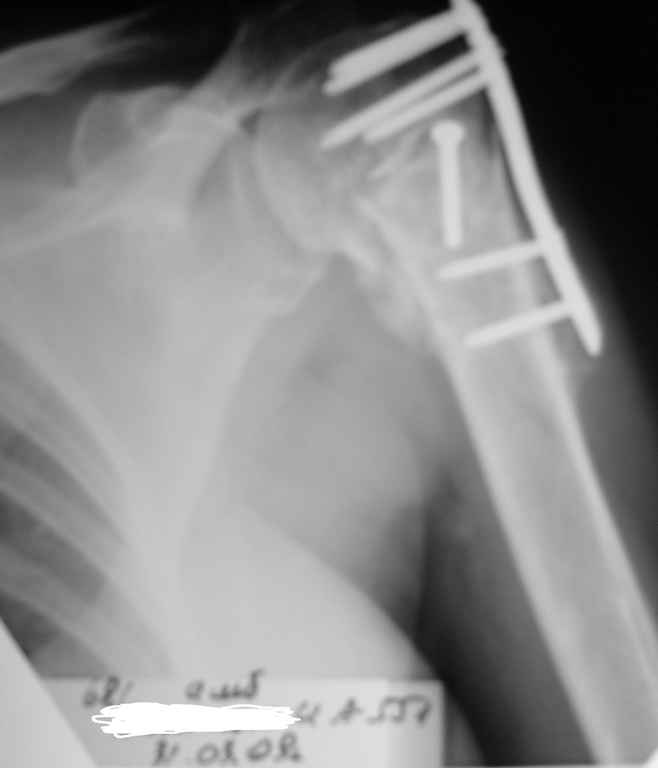

Здесь пример открытой репозиции 57 летнего с переломом плеча (1,2) смещение обнаружено на интероперационном снимке. При нормальной прямой проекция (3) угловое смещение обнаружили в аксиальной проекции (4)

После устранения смещения пластина установлена выше (5,6,7) и финальные снимки (8,9,10)

Подбор импланта тоже имеет значение, например многие импланты направлены для фиксации перелома без учета ротаторной манжетки. Предпочтительными являются низко сидящие полиаксиальные пластины, где верхние шурупы можно проводить под углом в 120 градусов. (11)

Пластина от Synthes или ее копии (надеюсь простят критику друзья из Деоста) считаются трудным из-за обширности доступа, особенно при установке верхне-заднего шурупа, где доступ надо расширять в верхнем отделе до ротаторной манжетки. Верхне сидящие импланты предназначены для проведения опоры (buttress) за бугристость плеча, но тогда приходится сталкиваться с подакромиальным импинжментом.

дополнительные снимки по протезированию